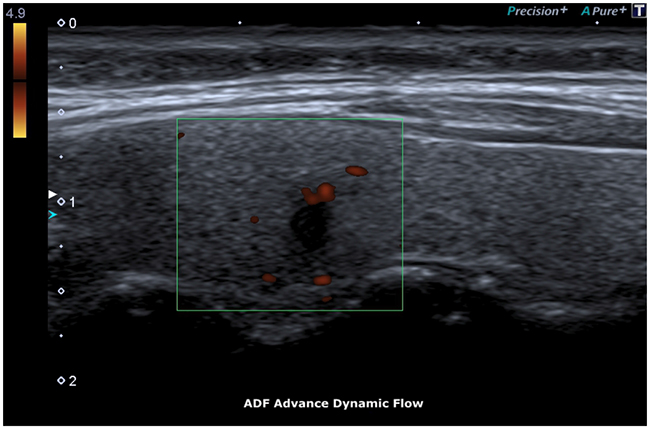

The ADF (Advanced Dynamic Flow) allows to underline the vessel flow of the newly formed tortuous vessels [14].

ADF test showed a clear flow through newly formed tortuous vessels at the periphery of the specific micro-focus (Figure 6, 7).

Figure 6: ADF, Advance Dynamic Flow.

The ADF allowed detection of microvascularization at the periphery of the micro-focus with accuracy.